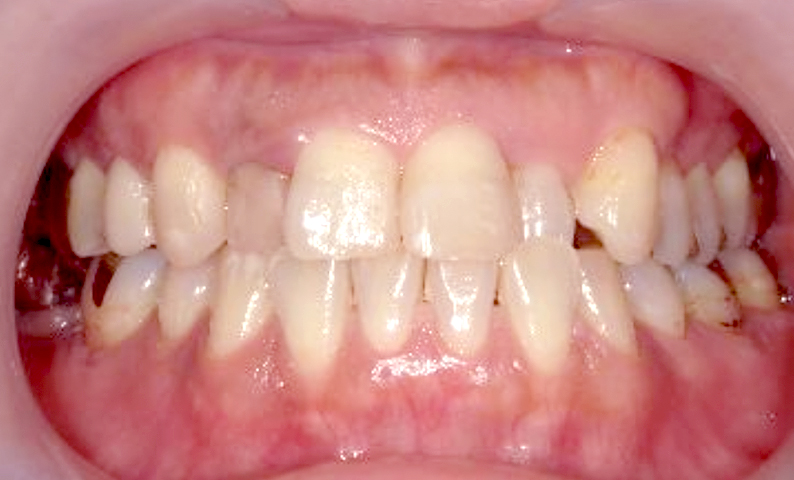

症例_001 上下顎の部分矯正

治療期間:12ヶ月金額:54万円+税女性反対咬合前歯のガタガタ

| Before | After |